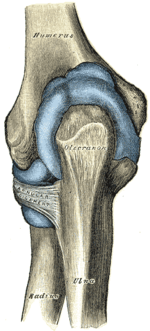

Left: anterior and ulnar collateral ligaments

Right: posterior and radial collateral ligaments

The elbow, like other joints, has ligaments on either side. These are triangular bands which blend with the joint capsule. They are positioned so that they always lie across the transverse joint axis and are, therefore, always relatively tense and impose strict limitations on abduction, adduction, and axial rotation at the elbow.[7]

The ulnar collateral ligament has its apex on the medial epicondyle. Its anterior band stretches from the anterior side of the medial epicondyle to the medial edge of the coronoid process, while the posterior band stretches from posterior side of the medial epicondyle to the medial side of the olecranon. These two bands are separated by a thinner intermediate part and their distal attachments are united by a transverse band below which the synovial membrane protrudes during joint movements. The anterior band is closely associated with the tendon of the superficial flexor muscles of the forearm, even being the origin of flexor digitorum superficialis. The ulnar nerve crosses the intermediate part as it enters the forearm.[7]

The radial collateral ligament is attached to the lateral epicondyle below the common extensor tendon. Less distinct than the ulnar collateral ligament, this ligament blends with the annular ligament of the radius and its margins are attached near the radial notch of the ulna.[7]